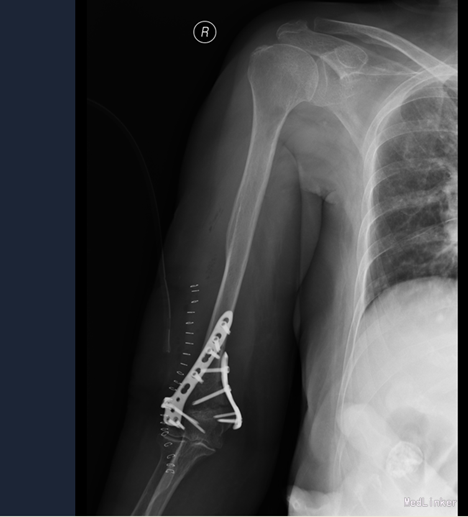

诊断:右肱骨骨折 治疗:切开复位内固定术

术后给予抗炎之疼等对症治疗,指导患者功能锻炼,术后每个月复查